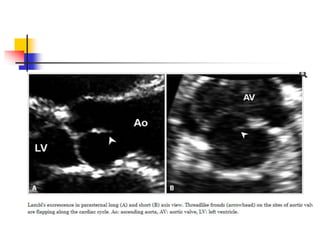

 Fine filamentous strands, Lambl excrescences, can

be seen originating from the aortic valve of elderly

patients.

 It is considered as a degenerative change on the

surface of leaflets due to mechanical wear and tear.

 Multiple adjacent excrescences may stick together

and grow up to large, complex form called "giant

Lambl's excrescence". Whether the excrescences

may serve as a nidus for bacterial growth or cause a

systemic embolism is controversial.

 In echo, it appears as very thin, delicate, lint-like mobile

threads arising from the free borders or ventricular

surfaces of aortic leaflets . Improving image quality

increases to find this lesion.

 significance of Lambl's excrescences lies in the

differential diagnosis from the vegetation of infective

endocarditis.

 It is challenging in most cases, and a diagnostic decision

making often depends on clinical settings.